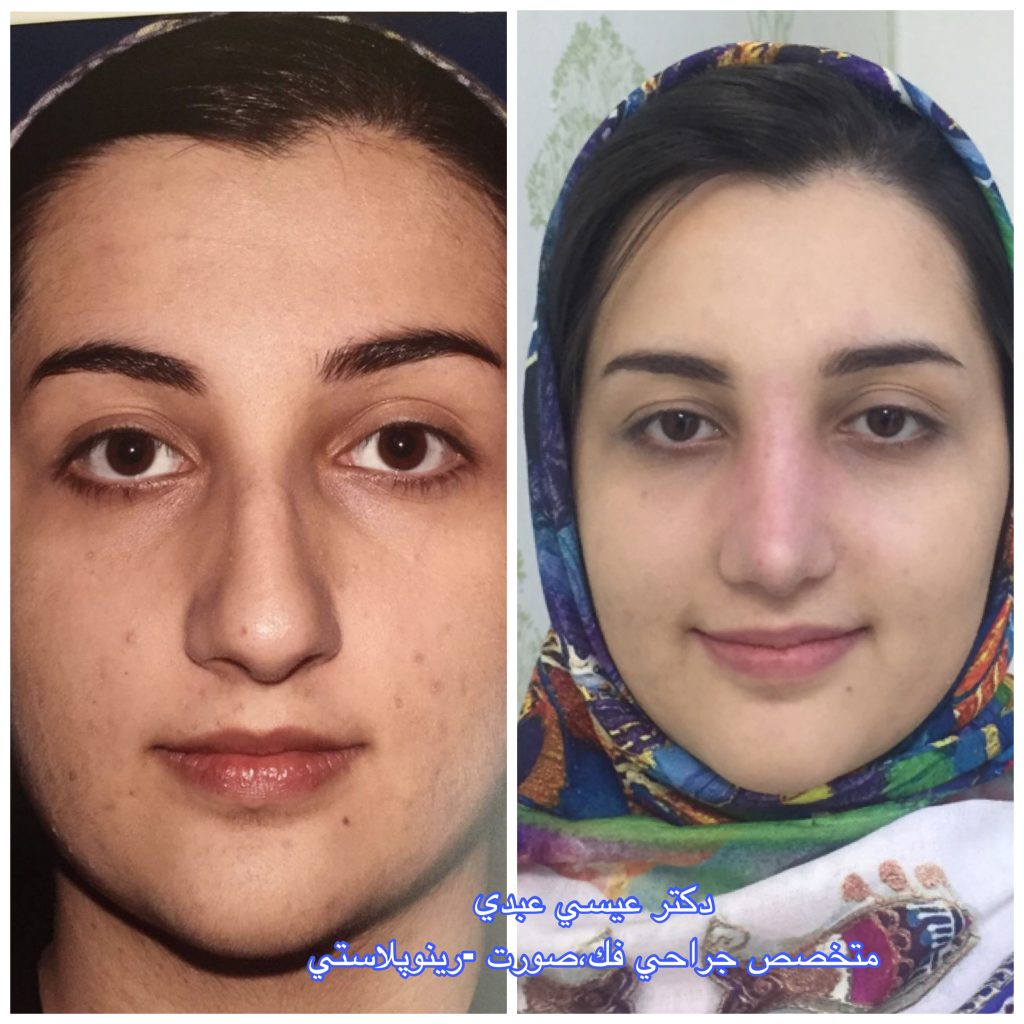

دکتر عیسی عبدی در رشت

دکتر عیسی عبدی در رشت

– متخصص جراحی فک , پلاستیک صورت و بینی

دکتر عیسی عبدی در رشت

جراحی فک , پلاستیک , صورت وبینی